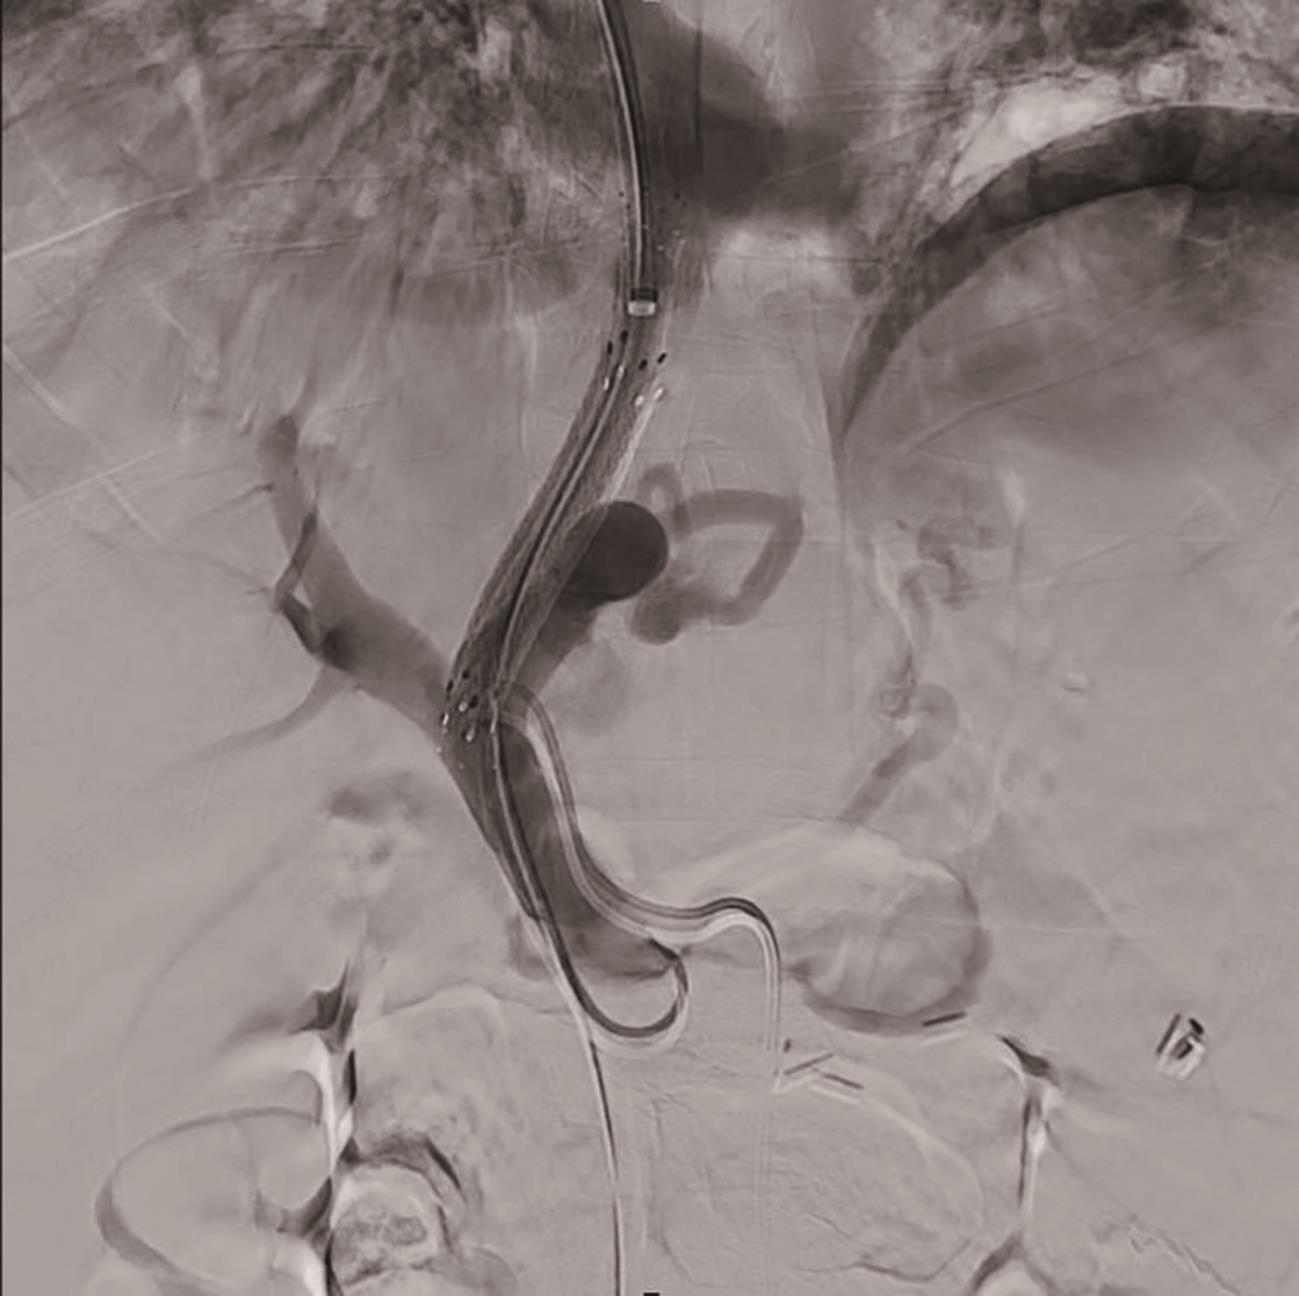

Diagnosis and treatment of decompensated cirrhosis with multiple primary cancers: A case report

2024, 40(9): 1868-1872. DOI: 10.12449/JCH240923

Abstract(927) HTML (392) PDF (1776KB)(108)

Abstract:

Multiple primary cancers (MPC) refer to the presence of more than one type of cancer with different histological features and sites in the same individual, and it is relatively rare in clinical practice. This article reports a case of decompensated cirrhosis with MPC and discusses the diagnosis, treatment, and clinical implications of this patient with decompensated cirrhosis and MPC.